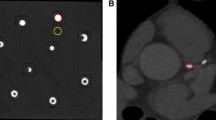

This is used e.g. in renal imaging, where iodine contrast agent is commonly applied for examinations of the renal parenchyma (e.g. for detection and characterization of tumors), to illustrate the arterial blood supply of the kidneys (e.g. for detection of artery stenosis or bleeding) and to visualize the urinary tract using delayed phase images, when the contrast agent passed the kidney and is visible within the ureter (e.g. to rule out ureteral obstruction). Fig. 1(a) shows CTs of a patient with a kidney stone in the ureter (indicated by the white arrow), which could block urine flow. To decide on further treatment, iodine contrast agent is injected into the blood stream to contrast the urine flow through the ureter after the contrast agent has been filtered from the blood. Yet, the contrast agent in the ureter gives a similar absorption signal as the kidney stone so that the discrimination of the two can only take place by taking two CT scans, a non-contrast scan before the injection of the contrast agent and one with contrast agent in the excretory phase. These have to be taken with a sufficient time span between them to ensure having contrast agent in the ureter in the contrasted scan.

Clinical X-ray CT images before (a) and after (b) administration of iodine contrast agent. In the CT image in (a) the kidney stone is clearly visible in the proximal part of the right ureter. However, after the injection of contrast agent (b) the kidney stone in the ureter cannot be distinguished from the iodine contrast agent and would be missed.

In conventional X-ray imaging, the image contrast arises from variations in absorption of different materials. Thereby, the absorption is dependent on the elemental composition and density of the material, leading to a strong contrast between bone and tissue structures. Yet, the elemental composition of soft tissues is rather similar and the attenuation contrast is weak. In subtraction X-ray imaging, tissue structures or organs are visualized using a contrast medium that changes the attenuation between the contrasted structure and the surrounding tissue4. In K-edge subtraction (KES) imaging, first proposed by B. Jacobson in 19535, two X-ray images are taken at different mean energies slightly below and a bit above the K-edge of the photoelectric absorption of the contrast medium. Their subtraction generates an image only displaying the contrasted structure while other anatomical structures or bones are eliminated as their attenuation stays basically constant. This can solve issues where the attenuation of a tissue was enhanced such by a contrast agent that it becomes indistinguishable from another structure. Commonly, this is the case with iodine-based contrast agent and calcium in calcifications or kidney stones (Fig. 1b). Although KES imaging at a polychromatic laboratory source has been demonstrated recently using a Ross filter arrangement6 or a multi-bin photon counting detector7,8, there are disadvantages such as the absorption of a large amount of the X-ray flux in the filter pairs leading to long acquisition times. Also the development of 2D pixelated spectroscopic detectors allow KES imaging at a laboratory X-ray source9,10. However, in some of these applications the sample is irradiated with a much broader beam than needed for the selected energy bins causing unnecessary radiation dose. In the past, KES imaging has usually been performed at synchrotrons.